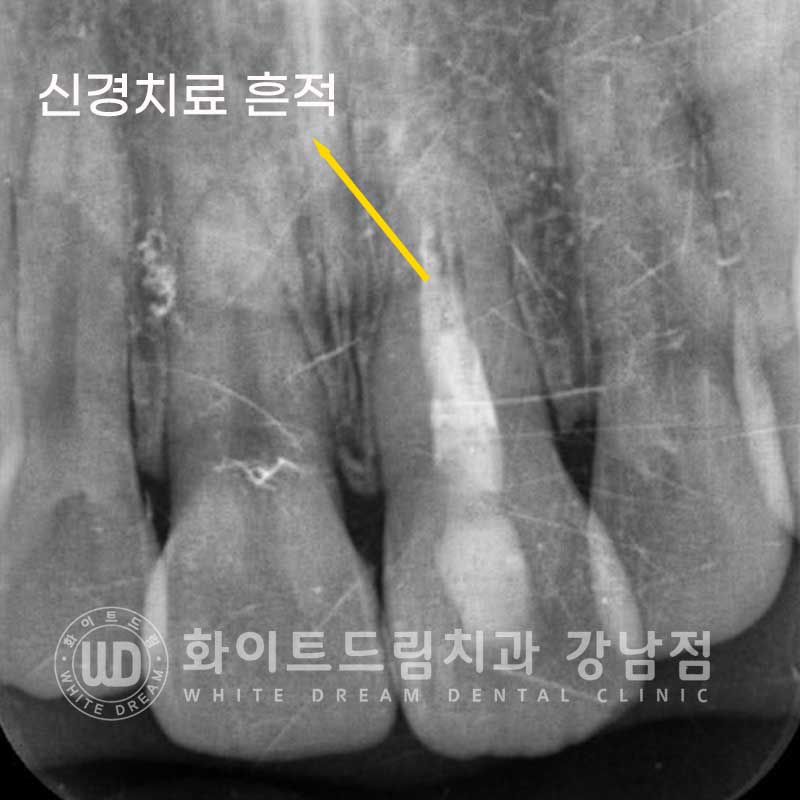

신경치료를 받은 치아는 내부 혈관과 신경이 제거된 상태로

자연치아에 비해 굉장히 약한 상태입니다.

그래서 보통 신경치료 후 크라운 치료를 진행해 약해진 치아를 보호해 주게 되는데요.

신경치료를 받은 치아, 왜 변색이 될까요?

신경치료는 앞서 말씀드린 대로 신경과 치아 내부 혈관을 모두 제거하는 진료입니다.

신경치료를 진행하는 과정에서 내부 출혈이 발생할 수 있는데

치료 후 남아있던 적혈구들이 변색이 되면서 겉으로 비춰 보이는 경우가 흔합니다.

혹은 신경치료 시 사용되는 재료들에 의해 변색이 일어날 수도 있답니다.